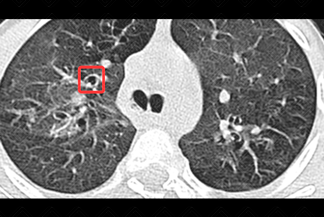

Texto alternativo para a imagem

Texto alternativo para a imagem Créditos: Dra. Elazir Mota - Rio de Janeiro/RJ.

Descrição das imagens: Paciente infantil, sexo masculino, 11 anos, em acompanhamento de fibrose cística. Na tomografia de tórax observam-se extensas bronquiectasias varicosas (setas brancas).